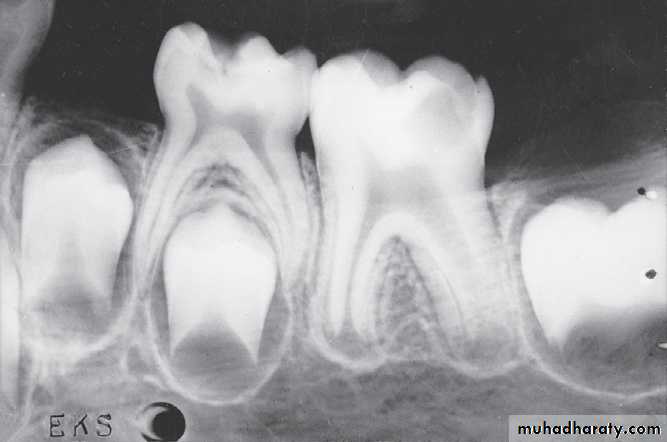

A, Pulp of the fi rst permanent molar was exposed by caries. The tooth was considered a candidate for the calcium hydroxide pulpotomy technique.

B, Calcifi ed

bridge has formed over the vital pulp in the canals.C, Continued

root development and pulpal recession are indicative of continuing pulpal vitality. The crown should be supported with a full-coverage restoration.Mature and immature teeth in the x-ray

Closed apex maxillary central incisors (mature)Open apex maxillary central incisors (immature)